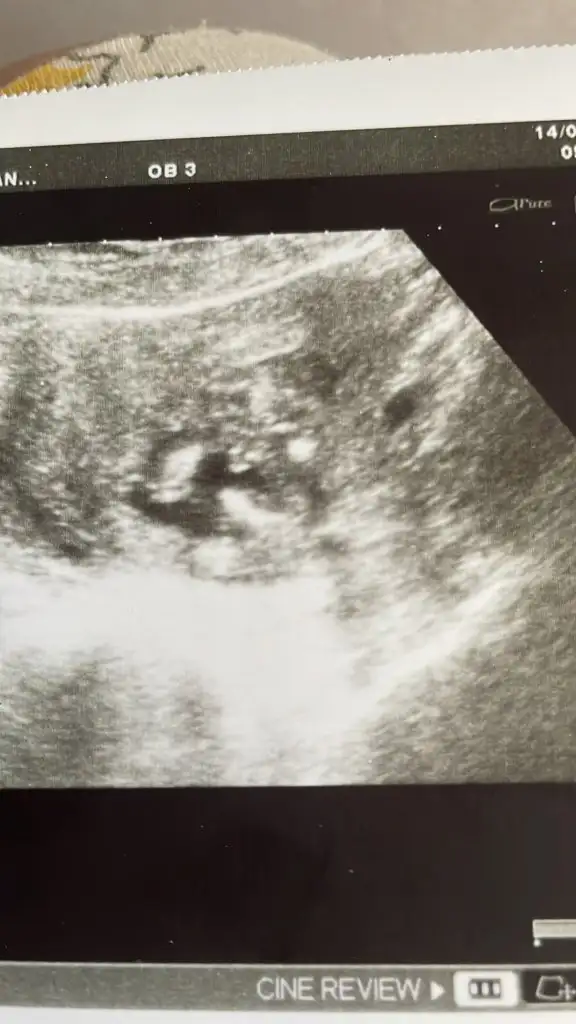

İlerleyen zamanlarda daha da iyi olursunuz inşallah. Bizim bacak arası bir öyle bir böyle emin değiliz bu yüzden . Bakın tekrar atayım. Bacak arasındaki kordon mudur artık ayrıntılıda çıkacakAmin canım benim, evet benimki büyük olasılıkla kız doktor bacak arası çıkıntı göremiyorum dedi

Çok sağolun amin. Evet sizin bebeğinizdeki çıkıntı benimkisine göre daha fazla. Erkek olma olasılığı da var. O nedenle biraz daha beklemek en iyisi. Dediğiniz gibi bazen kordon yanıltabiliyor.İlerleyen zamanlarda daha da iyi olursunuz inşallah. Bizim bacak arası bir öyle bir böyle emin değiliz bu yüzden . Bakın tekrar atayım. Bacak arasındaki kordon mudur artık ayrıntılıda çıkacak